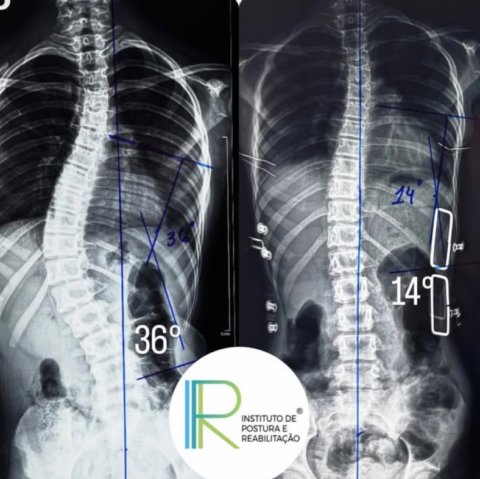

1. Observação e/ou acompanhamento preventivo – para casos de 0 a 10 graus;

2. Tratamento com exercícios específicos, RPG – para 10 a 25 graus;

3. Tratamento com colete e exercícios específicos, RPG – de 25 graus a 45 graus;

4. Tratamentos cirúrgicos – para curvaturas maiores de 45 e 50 graus.

Os tratamentos de escoliose de forma conservadora têm melhores resultados quando a condição é detectada precocemente e tratada com métodos apropriados e comprovados, com exercícios estáticos e dinâmicos podem desempenhar um papel importante na desaceleração, parada da progressão e correção da escoliose idiopática infantil. O sucesso vai depender de diferentes fatores, inclusive, da gravidade da curvatura.